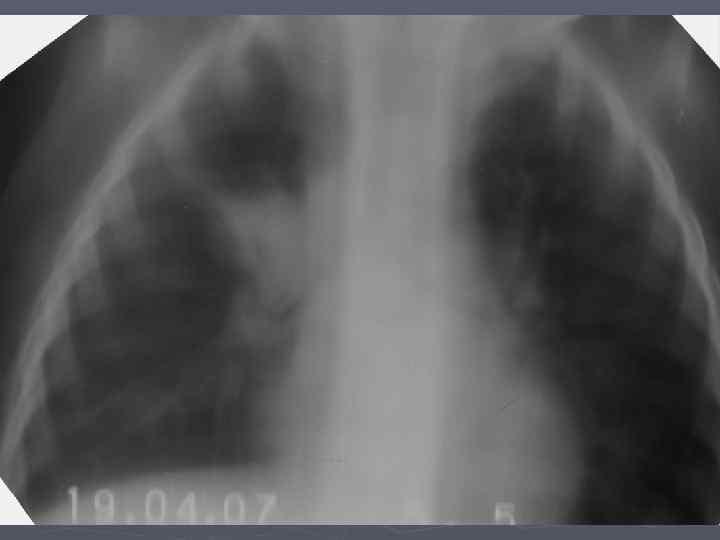

Клинические особенности туберкулеза у взрослых на фоне ВИЧ-инфекции ► ► ► ► ► Внутригрудные аденопатии; Милиарные высыпания; Частое поражение базальных сегментов легких; Относительно редкое поражение каудоапикальных сегментов легких; Распад легочной ткани диагностируется в 2 раза реже; Нередок плевральный выпот; Велика склонность к генерализации туберкулезной инфекции с множественными внелегочными локализациями. Присоеднинение туберкулезного менингита; МБТ в мокроте выявляются одинаково часто у ВИЧ негативных и позитивных лиц, по крови МБТ методом посева выделяются у 70% пациентов; При отсутствии признаков локального туберкулеза и неясной лихорадке – посев костного мозга часто дает МБТ+.

Клинико-эпидемиологические особенности туберкулезной инфекции у ВИЧинфицированных и больных СПИДом детей ► Вертикальный путь заражения ВИЧ; ► Ранний возраст; ► Семейные контакты с болеющими туберкулезом в активных фазах; ► Отсутствие вакцинации БЦЖ; ► Выраженный локальный процесс, протекающий с: § бронхолегочными поражениями; § Распадом легочной ткани; § Обсеменением легочной ткани.

Неблагоприятное сочетание ряда обстоятельств: § Ранний возраст; § Тяжелые семейные контакты; § Отсутствие вакцинации - и у свободных от ВИЧ-инфекции детей всегда приводят к развитию локального туберкулеза, протекающего, как правило, ОСЛОЖНЕННО с бронхолегочными поражениями, распадом легочной ткани, диссеминациями.